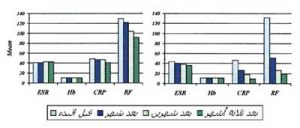

يوضح الرسم تأثير العلاج المزدوج والعلاج الدوائي منفردا على مؤشرات نشاط المرض اللإكلينيكية في كل مجموعة

يوضح الرسم تأثير العلاج المزدوج والعلاج الدوائي منفردا على مؤشرات نشاط المرض اللإكلينيكية في كل مجموعة

أولاً: نتائج الفحص الإكلينيكي (السريري) لدلالات نشاط الروماتويد:

• قبل البدء بالعلاج:

ثبت إحصائيا عدم وجود فارق ذا دلالة إحصائية بين المجموعتين من حيث مؤشرات (دلالات) نشاط الروماتويد الاكلينيكية( سجل شدة الألمVAS وعدد المفاصل المتورمة SJC والمؤلمة TJC بالإضافة إلى سجل نشاط المرض (DAS28.

• بعد ثلاثة أشهر من العلاج:

انخفضت بشكل ملحوظ مؤشرات (دلالات) نشاط المرض اللإكلينيكية في كل من المجموعتين ولكن كان الانخفاض سريعا في مجموعة العلاج المزدوج (بعد الشهر الأول من اضافة الحجامة إلى العلاج الدوائي) بينما كان الانخفاض متأخرا في مجموعة العلاج الدوائي (بعد الشهر الثالث من العلاج الدوائي منفردا).

ثانياً: نتائج الفحص المعملي لدلالات نشاط الروماتويد :

• قبل البدء بالعلاج:

ثبت إحصائيا عدم وجود فارق ذا دلالة إحصائية بين المجموعتين من حيث مؤشرات (دلالات) نشاط الروماتويد المعملية (سرعة ترسيب الكرات الحمراء , والبروتين المتفاعل سي, ومعامل الروماتويد) .

• بعد ثلاثة أشهر من العلاج:

1. لم يثبت إحصائيا أي تغير في معدلات سرعة الترسيب ESR في مجموعة العلاج الدوائي . بينما ثبت إحصائيا إنخفاض في معدلات سرعة الترسيب بعد الشهر الثالث من استخدام العلاج المزدوج. يعتبر معدل سرعة الترسيب مؤشرا على درجة الالتهاب وهو أحد دلالات نشاط المرض المهمة التي يتم متابعة نشاط المرض من خلالها.

2. ثبت إحصائيا حدوث إنخفاض في تركيز خضاب الدم (الهيموجلوبين) Hb بعد ثلاثة أشهرمن تلقي العلاج الدوائي منفردا . في المقابل ارتفع تركيز خضاب الدم ارتفاعا طفيفا في مجموعة العلاج المزدوج غير أن ذلك الارتفاع لم يكن ذا دلالة إحصائية.

3.انخفضت بشكل ملحوظ معدلات البروتين المتفاعل سيCRP -وهو أحد المؤشرات المعملية لنشاط للمرض- في كل من المجموعتين ولكن كان الانخفاض كبيرا و سريعا في مجموعة العلاج المزدوج (بعد الشهر الأول من اضافة الحجامة إلى العلاج الدوائي) مقارنة بمجموعة العلاج الدوائي.

4. ثبت إحصائيا وجود انخفاض هائل وسريع في معامل الروماتويد RF في مجموعة العلاج المزدوج وهذا يدل على أن الحجامة تحدث تأثيرا تنظيميا على الجلوبينات المناعية . ما قد يشير إلى تأثير الحجامة على المناعة الخلطية Humoral Immunity. بينما جاء انخفاض معامل الروماتويد قليلا ومتأخرا في مجموعة العلاج الدوائي (بعد الشهر الثالث من العلاج الدوائي منفردا).